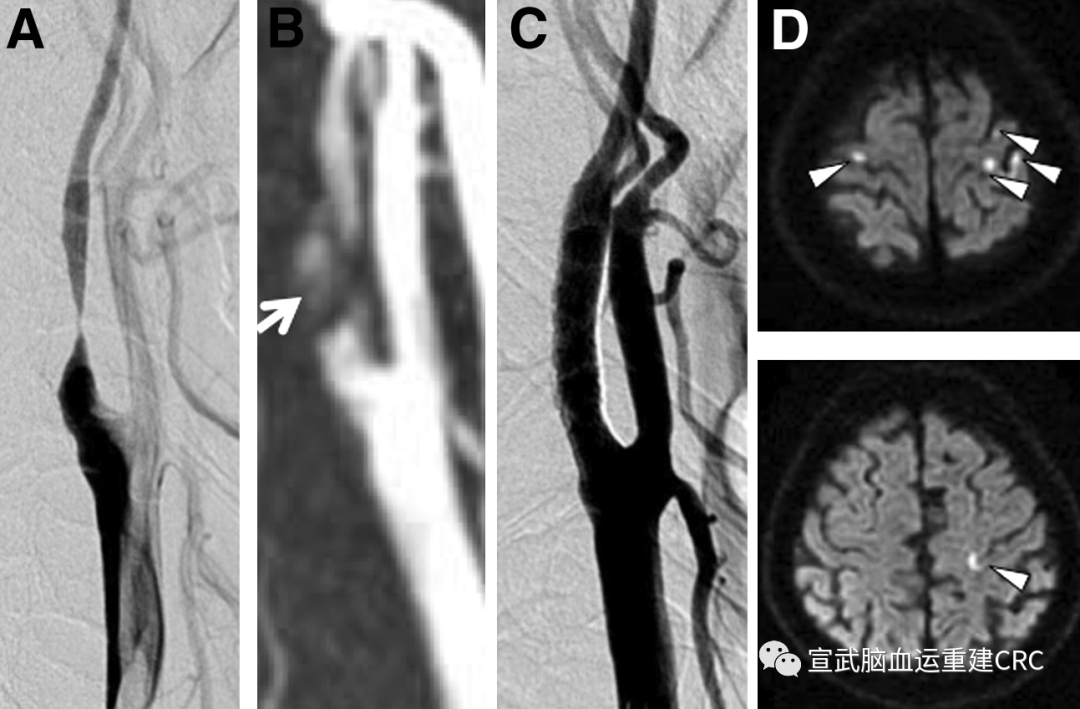

CAS治疗有效标准:支架置入后,造影所示残余狭窄<30%。

主要研究终点:术后7天内,同侧DWI新发梗死灶发生率。

次要研究终点:

围术期卒中、急性心梗、死亡等严重不良事件;

术后任何出血事件、急性肾功能损伤等手术相关并发症;

术后7天,同侧DWI新发梗死的数量、体积和部位;

术后7天,对侧DWI新发梗死的数量、体积和部位;

以我们的研究为例,首选角度是卒中、心梗或者死亡。选择30天内作为指标是最合适,但是围手术期发生卒中、心梗或者死亡虽然概率很低,如果说要照这个标准去设计试验,可能要做几千例非常大规模地去做,对于外科手术来说,这样操作来说这不现实。

于是我们退而求其次,选择DWI上新发梗死作为一个替代指标。这个替代指标和我们之前说的硬指标临床结局之间,有没有明确的相对关系?只能说这样的一个影像学的表现是目前被公认的,认为是新发梗死非常重要的影像学表现。

由此,我们选择了替代指标,当我们选择替代指标去作为主要结局时,是很具有风险的。我们得到的证据可能就没有那么重要,对于整个治疗来说,试验在设计的时候就考虑到可行性。我们只能去选择影像学指标作为替代指标,我们就确定了这个结局。

主要研究终点就以影像学的指标作为研究终点。次要研究终点是卒中、心梗和死亡这些事件作为次要终点纳入。